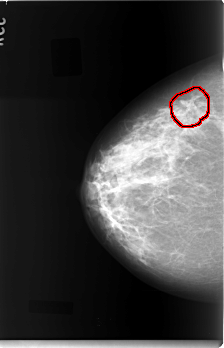

C_0032_1.RIGHT_CC

RIGHT_CC LINES 5912 PIXELS_PER_LINE 3800 BITS_PER_PIXEL 12 RESOLUTION 50 OVERLAY

FILE: C_0032_1.RIGHT_CC.OVERLAY

TOTAL_ABNORMALITIES 1

ABNORMALITY 1

LESION_TYPE MASS SHAPE ARCHITECTURAL_DISTORTION MARGINS ILL_DEFINED

ASSESSMENT 4

SUBTLETY 2

PATHOLOGY MALIGNANT

TOTAL_OUTLINES 1

BOUNDARY